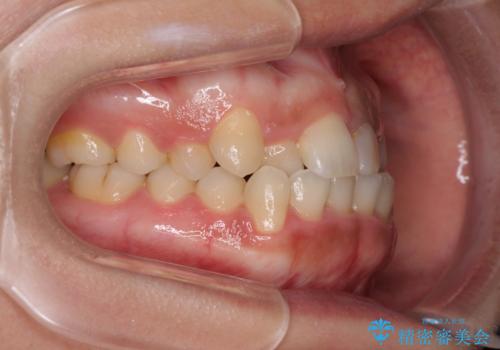

前歯のクロスバイトと変色した歯 ワイヤー矯正とセラミック治療

- 前歯のクロスバイトと神経を取り除いた後に変色してしまった前歯を気にして来院された患者様です。

ワイヤー矯正により矯正治療を行った後に、前歯の補綴治療を行うこととしました。